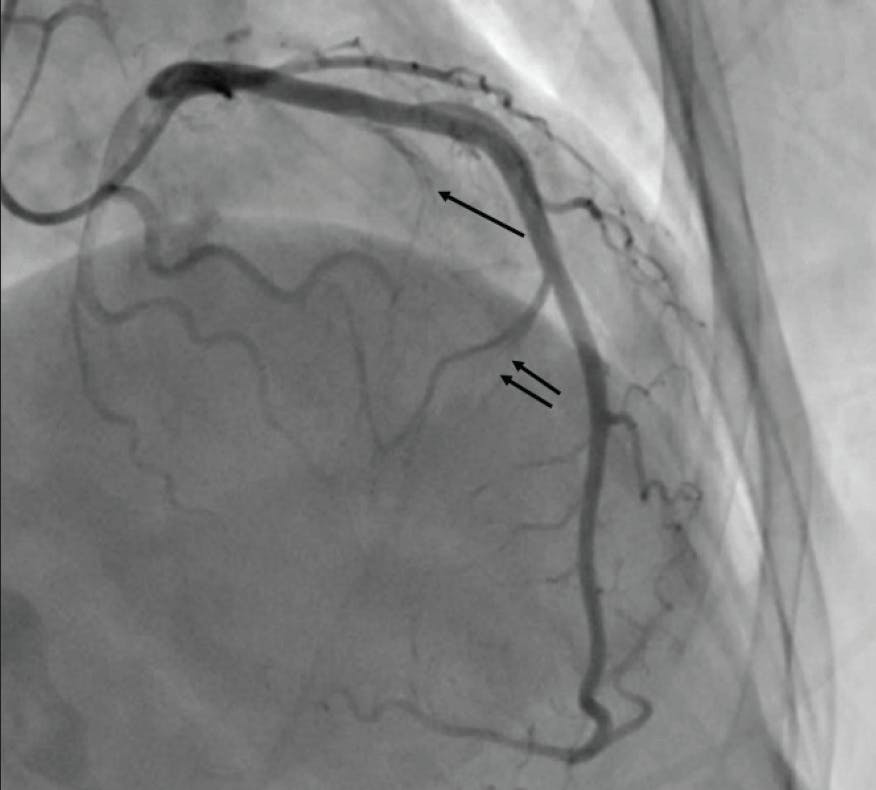

Figure 2. In this patient, the first septal perforator (single arrow) is a very small vessel, and injection with alcohol is unlikely to impact the gradient. A larger second septal perforator (double arrow) supplies the midseptum distal to the SAM contact point, and injection in this vessel will not impact the gradient.